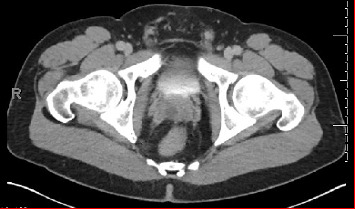

Seminal vesicle cyst (SVC) is a rare condition that can arise from congenital or acquired causes. In this report, we describe the case of a 33-year-old male who was incidentally discovered to have SVC and seminal vesicle stones following complaints of abdominal pain. He presented to the emergency department with these symptoms, which prompted further investigation and diagnosis. Computerized tomography (CT) scan revealed diverticulitis and a fluid attenuation lesion within the right aspect of the prostate gland. He was referred to urology, and further evaluation showed a right SVC of 1.8 × 1.5 × 1.5 cm on magnetic resonance imaging (MRI). The patient underwent endoscopic drainage of the SVC via transurethral seminal vesiculoscopy (TRU-SVS) and holmium laser incision. Three stones ranging from 2 to 4 mm were identified and removed with N-gage basket from the seminal vesicle resulting in successful removal of the stones and restoration of the ejaculatory duct's patency. Follow-up visits showed resolution of pain and an improvement in semen volume. This case report highlights the importance of considering SVC as a differential diagnosis in male patients presenting with such symptoms. TRU-SVS is a feasible and effective treatment option for SVC and associated seminal vesicle stones.